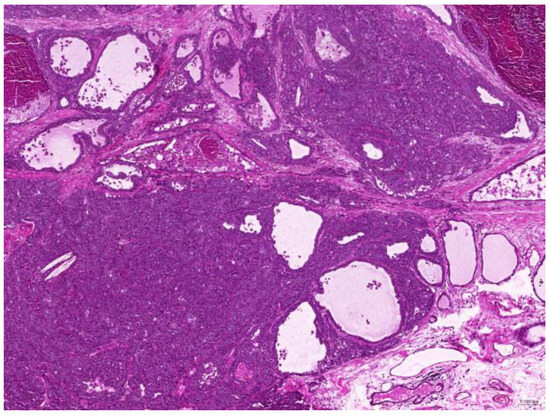

Of the 85 biopsy samples, the most commonly affected system was the integumentary system (48.2%, 41/85), followed by the reproductive system (42.4%, 36/85), the digestive system (8.2%, 7/85), and the urinary system (1.2%, 1/85) (Table 3). Of the 41 rabbits with an affected integumentary system, 39 had neoplastic and two had non-neoplastic disorders. The median age of these affected rabbits was 87 (12–149) months. There were 15 females and 26 males, with a female-to-male ratio of 0.54:1. The most common integumentary diagnosis was fibrosarcoma (29.3%, 12/41) (Figure 1), followed by trichoblastoma (19.5%, 8/41) (Figure 2), fibroma (9.8%, 4/41) (Figure 3), lipoma (7.3%, 3/41), mammary gland adenoma (7.3%, 3/41), and mammary gland adenocarcinoma (4.9%, 2/41) (Figure 4), among others. The median age of the rabbits with fibrosarcomas was 108 (54–126) months. Of the 12 cases with fibrosarcoma, 4 were females and 8 were males, with a female-to-male ratio of 0.5:1. The tumors were located on the neck, chest, abdomen, and extremities. The median age of the rabbits with fibromas was 101 (48–108) months. All four of these were males, with tumors exclusively located on the chest. Myxosarcoma was diagnosed in a 108-month-old male rabbit, with the tumor located on the left elbow (Figure 5).

Figure 5. Myxosarcoma. The neoplasm contains basophilic mucinous material (scale bar = 200 µm). Hematoxylin and eosin staining.